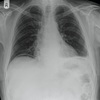

18

Q

¿Qué tipo de proyección es esta?

A

Proyección lordótica